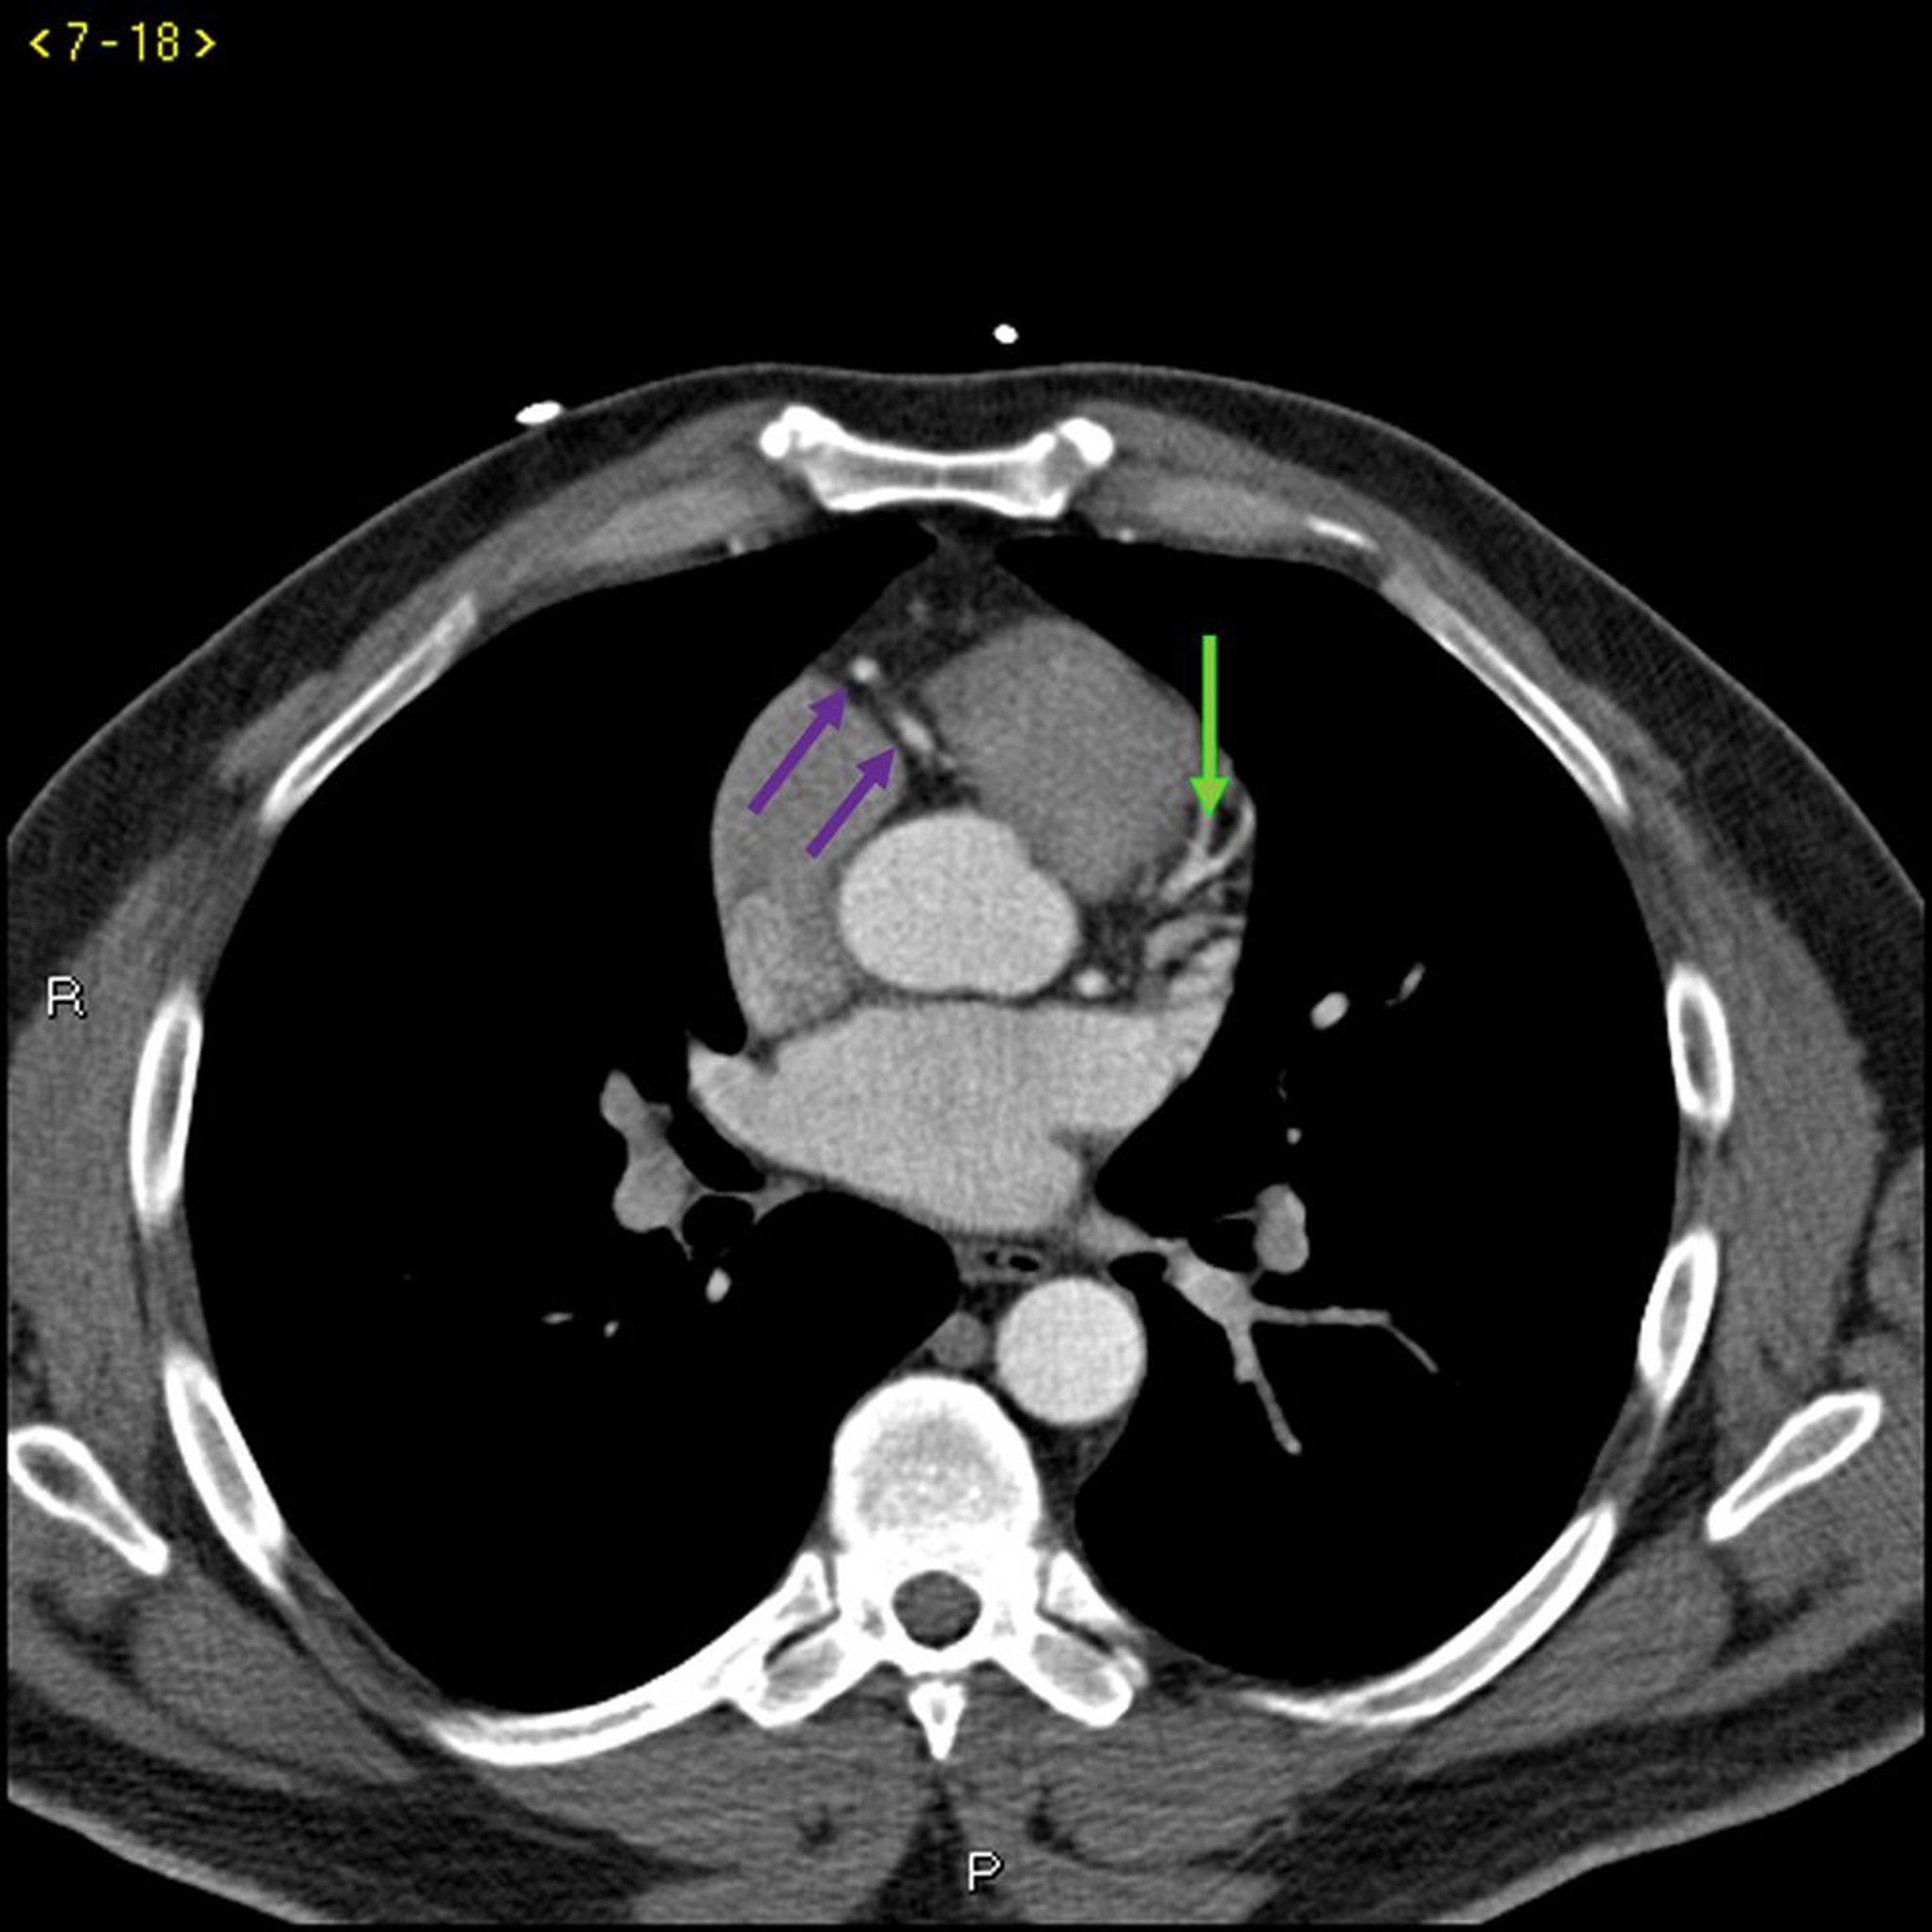

КТ с контрастированием, показывающая коронарные артерии в норме – слайд 3

КТ с контрастированием, показывающая коронарные артерии в норме Левая ветвь коронарной артерии обозначена красной стрелкой. Левая передняя нисходящая и левая огибающая артерии обозначены зеленой и синей стрелками соответственно, а правая коронарная артерия – филетовой стрелкой.